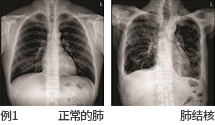

- 检查的目的 : 观察人体解剖学构造,观察骨骼上是否有骨节, 确认软组织是否存在异常,观察患病部位的进程。